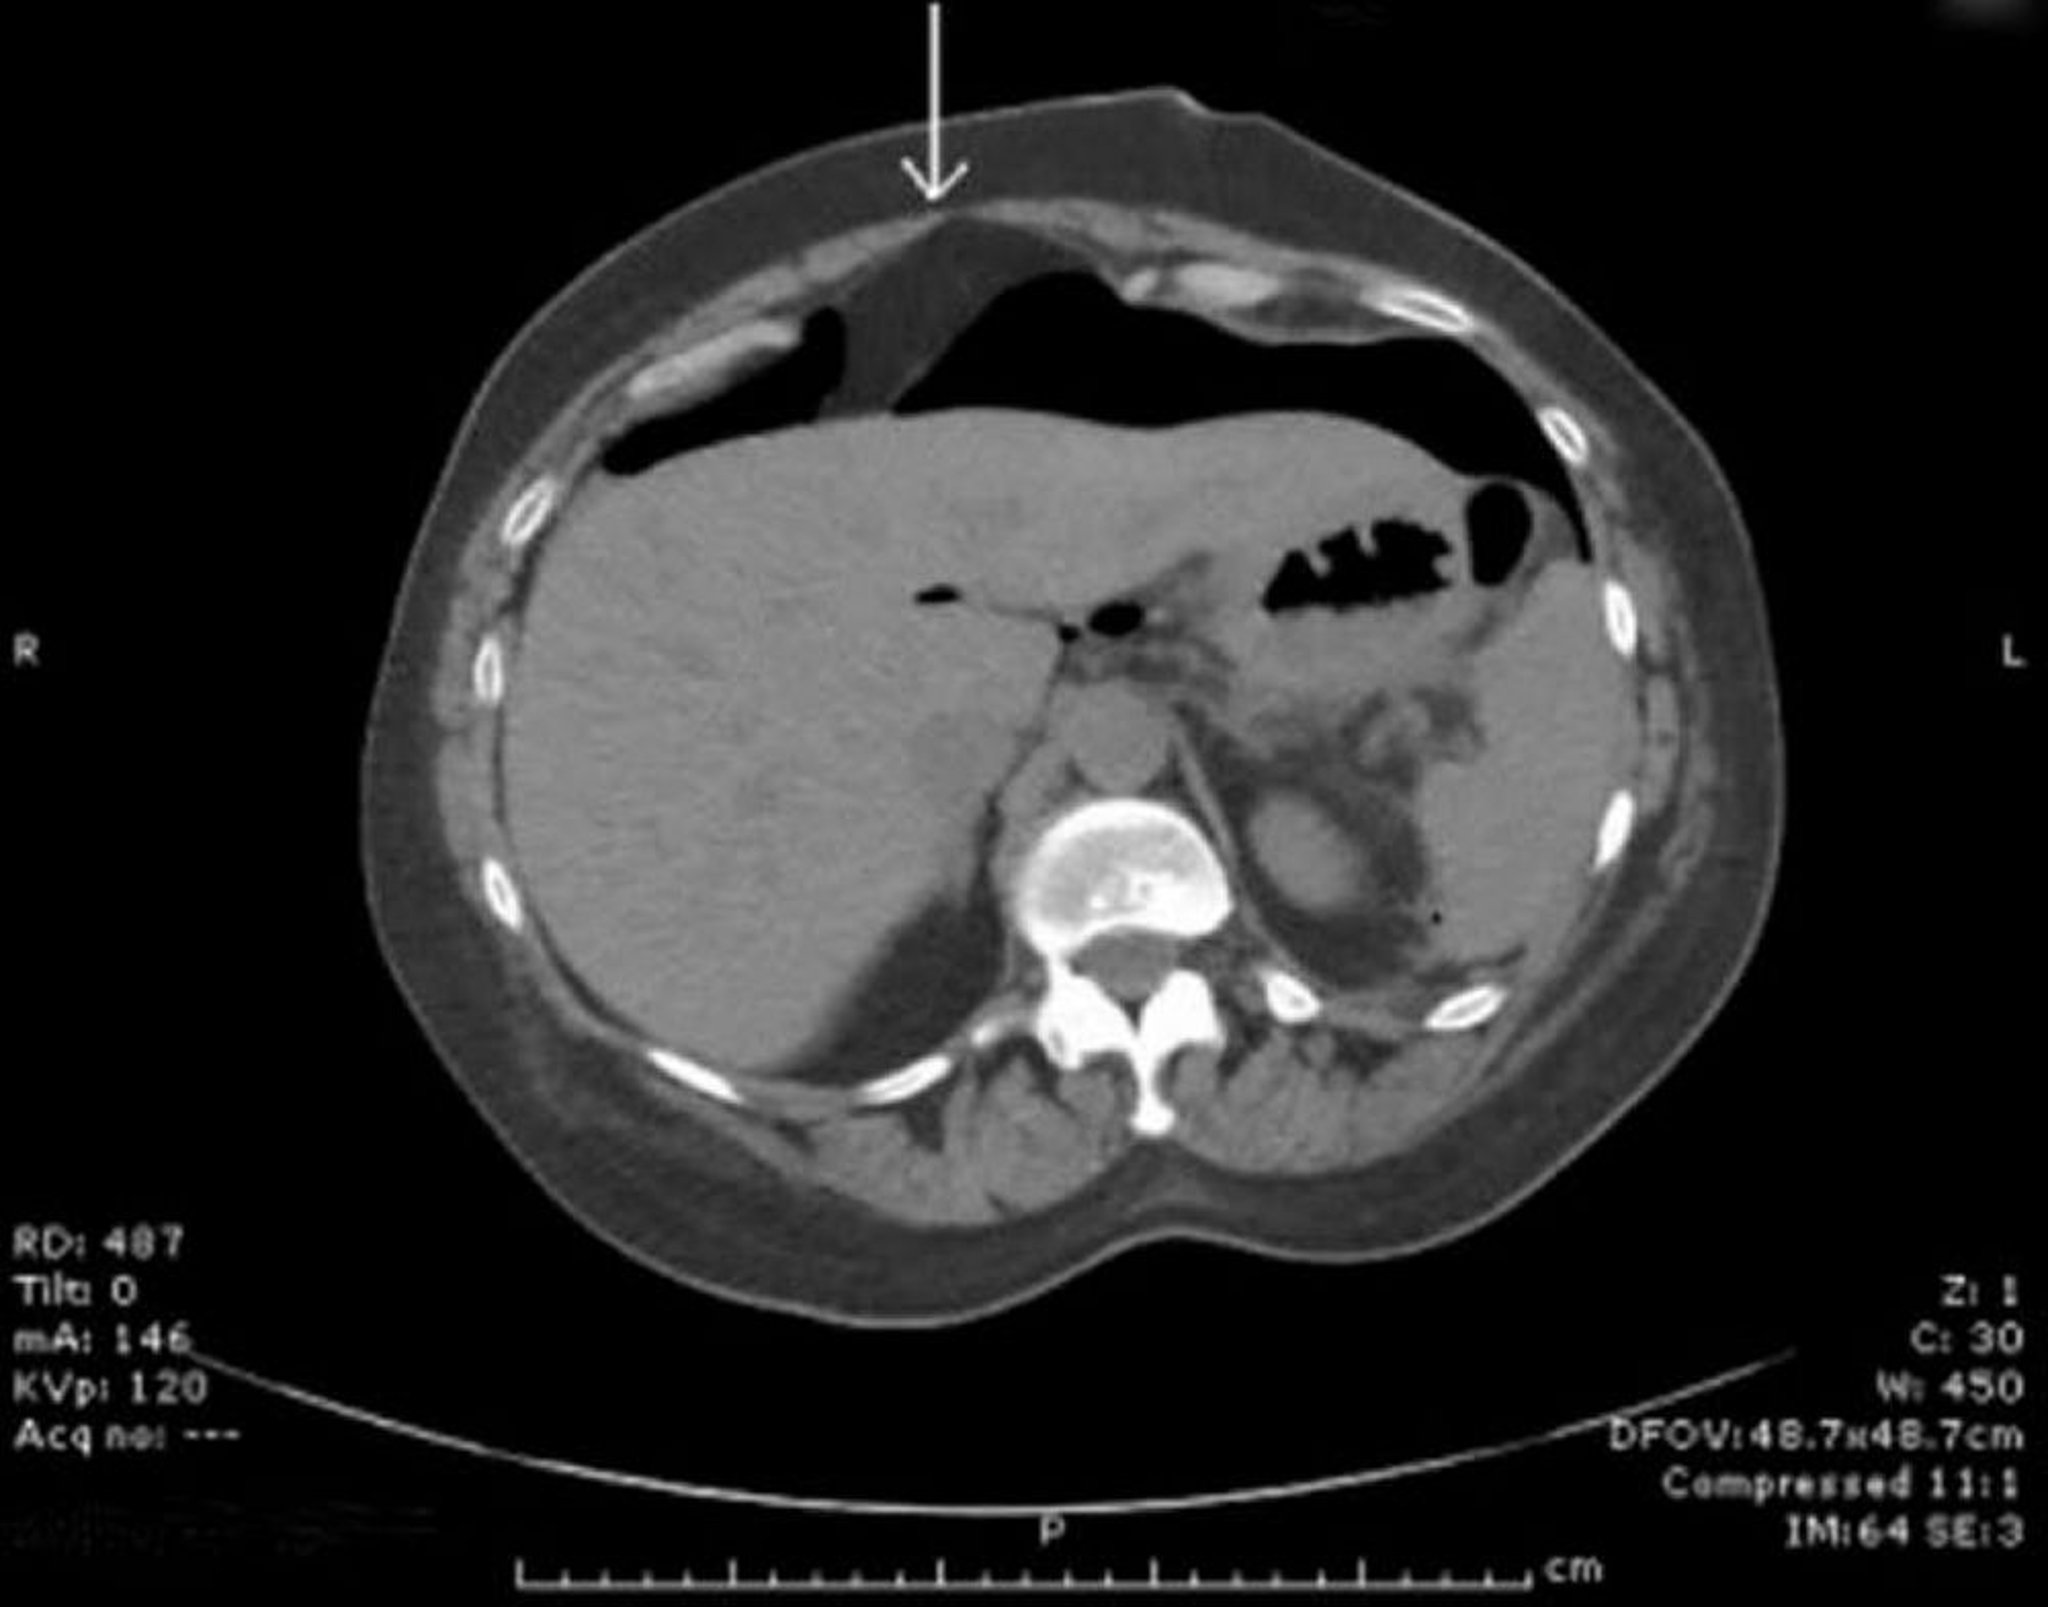

КТ с признаками свободного газа в брюшной полости

Перед печенью видно скопление воздуха. Стрелка указывает на серповидную связку.